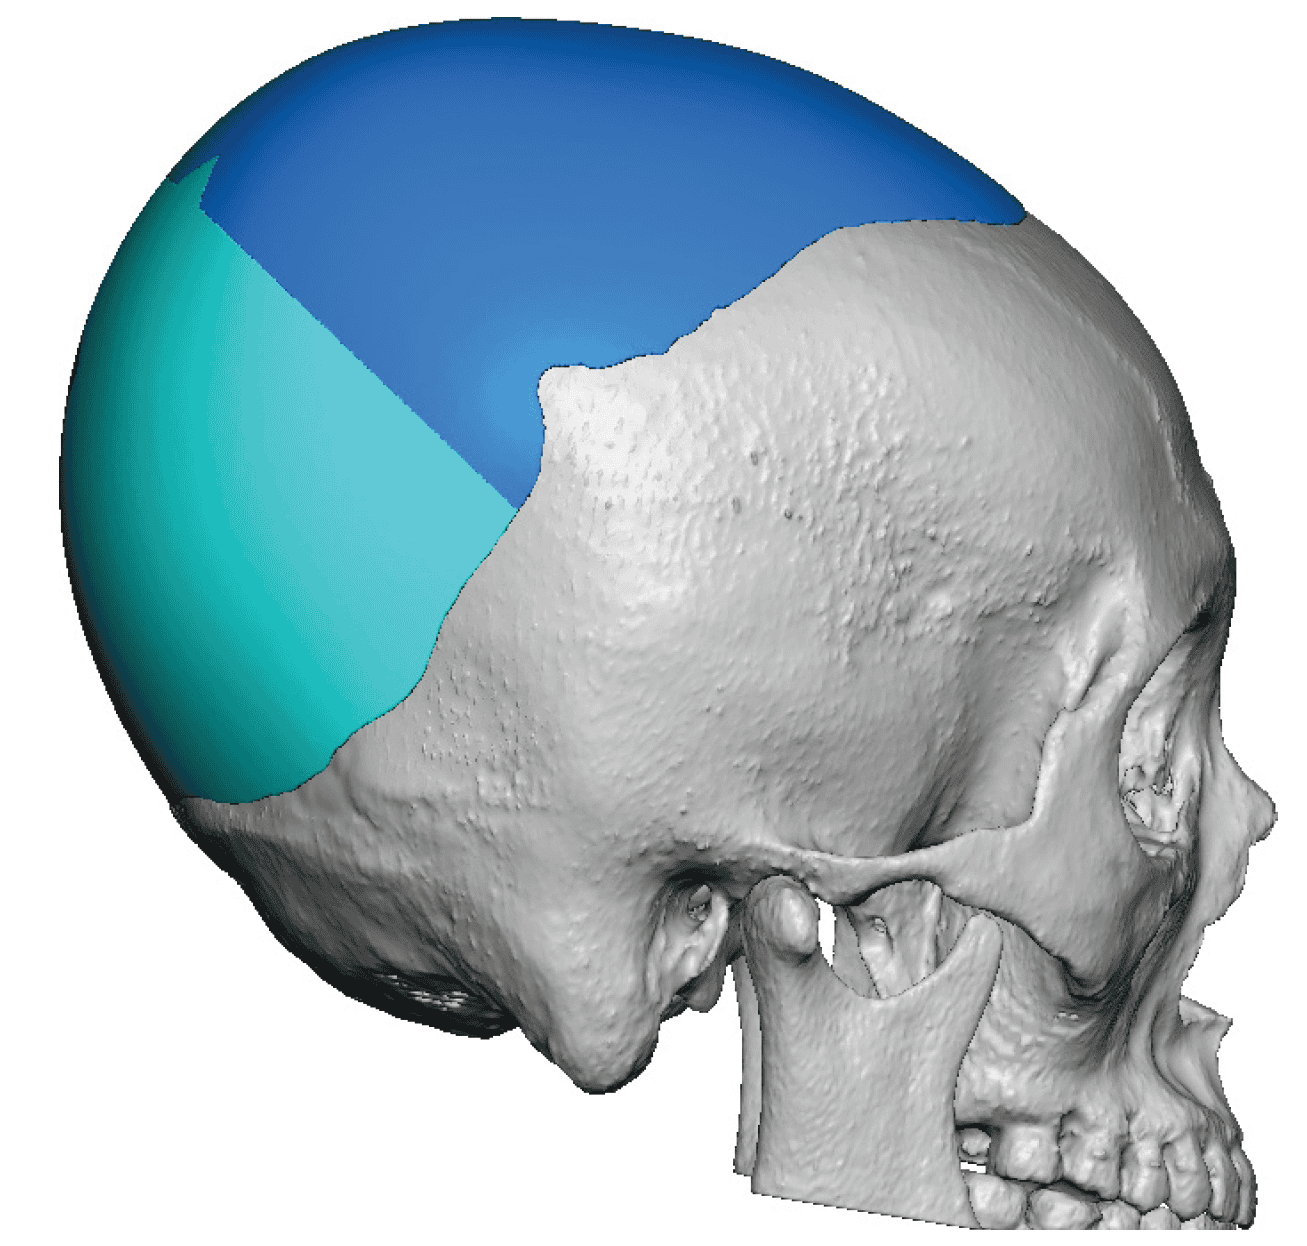

Patient 84

Desire for change of head shape from front view form an inverted V shape to a rounder and wider head shape.

Placement of custom extended forehead-temporal implants through incisions in the crease behind the ear. (he had a prior back of head skull implant which is green in the implant designs and which the head widening implants partially covered it)

Desire for change of head shape from front view form an inverted V shape to a rounder and wider head shape.

Placement of custom extended forehead-temporal implants through incisions in the crease behind the ear. (he had a prior back of head skull implant which is green in the implant designs and which the head widening implants partially covered it)